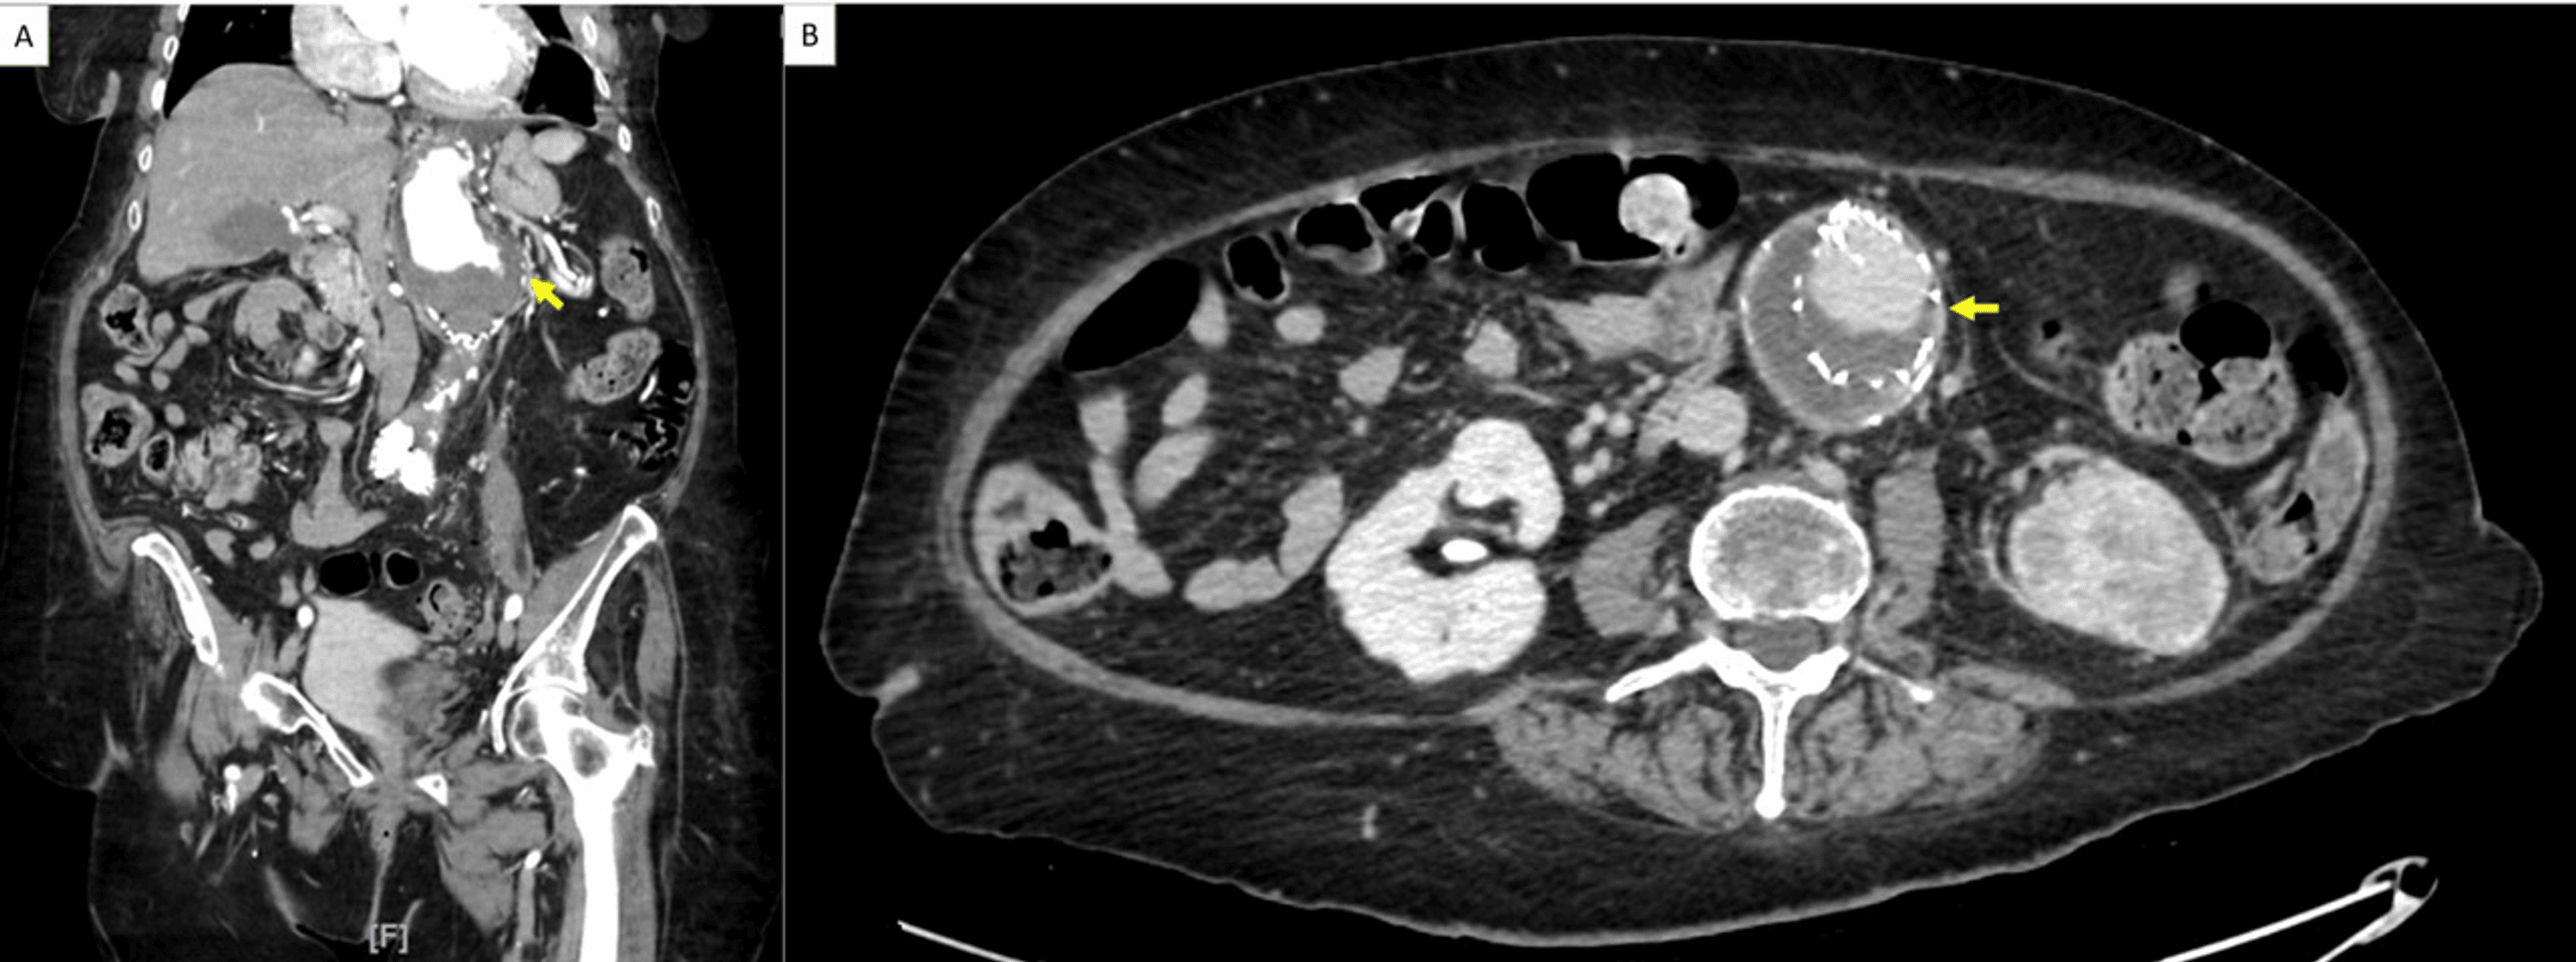

From www.cureus.com

Left Renal Artery Chronic Occlusion in the Setting of Extensive Define Chronic Mural Thrombus Future research should investigate (1) the natural history of mural (laminated) lv thrombus and whether the duration of. The advent of transesophageal echocardiography (tee) and magnetic resonance imaging (mri) and the more frequent use of computed tomography (ct) have led to the identification of. Mural thrombi are blood clots that form within the heart or blood vessels, often associated with. Define Chronic Mural Thrombus.